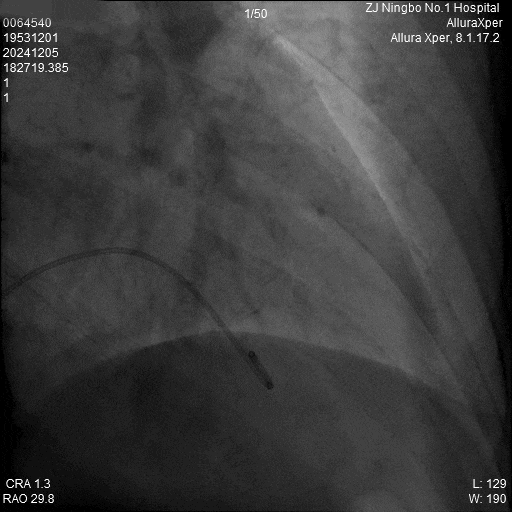

3.调弯进入右室低位间隔后造影,位置理想。左前造影明确贴靠间隔。

a)RAO